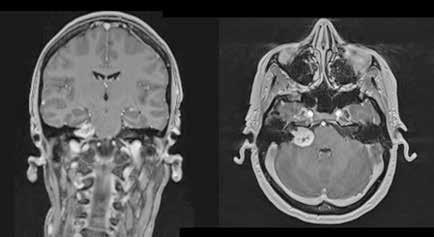

A las 36 horas de vida presenta nuevo empeoramiento respiratorio, se solicita estudio completo y se realiza punción lumbar (a pesar de paráme tros infecciosos negativos en la analítica). Se obtiene líquido purulento y se procede a escalada de tratamiento a ceftriaxona y ampicilina (mantiene tratamiento durante 7 y 3 días respectivamente, no aislándose microorga nismos en muestras de líquido cefalorraquídeo ni hemocultivos). Se repite la radiografía de tórax en la que se evidencia neumotórax de nueva apa rición e imagen sugestiva de neumomediastino. Ante estos hallazgos, se solicita TC de tórax que confirma el diagnóstico y descarta la existencia de causas desencadenantes (Figura 2). Se mantienen requerimientos de VMNI durante 4 días más, siendo finalmente posible la desescalada gradual a oxigenoterapia con gafas nasales durante 4 días. Se consigue retirada del soporte respiratorio de manera completa pasados 8 días, realizando un control con TC de tórax a los 9 días de vida (Figura 3) que muestra mejoría significativa acompañándose de una recuperación clínica completa.

Figura 1. (Izq.) radiografía de tórax en proyección anteroposterior (AP) al ingreso en UCI-N para comprobación de sonda nasogástrica sin hallazgos significativos. (Der.) Radiografía de tórax AP a las 16 horas de vida donde se objetivan tenues focos de aumento de densidad de distribución difusa, alguno de ellos, como el localizado en campo superior izquierdo, con broncograma aéreo.

Figura 2. (Izq.) radiografía de tórax en proyección AP a las 36 horas de vida donde se objetiva neumotórax de nueva aparición (flechas azules) y una zona de hiperclaridad alrededor de la silueta cardíaca que sugiere importante neumomediastino (estrellas amarillas). (Der.) TC de tórax sin contraste intravenoso en ventana de pulmón que confirma la presencia de neumomediastino (estrella amarilla). Se objetivan focos de consolidación periféricos y bandas lineales de densidad aire paralelas y adyacentes a las vainas broncovasculares (flechas amarillas).

Figura 3. TC de tórax sin contraste intravenoso en ventana de pulmón a los 9 días de vida sin alteraciones en el parénquima y neumomediastino prácticamente resuelto.